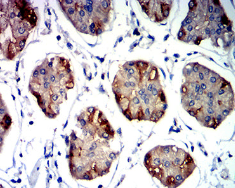

CD337 Mouse Monoclonal antibody[2D3B1]

IHC    1/200 - 1/1000